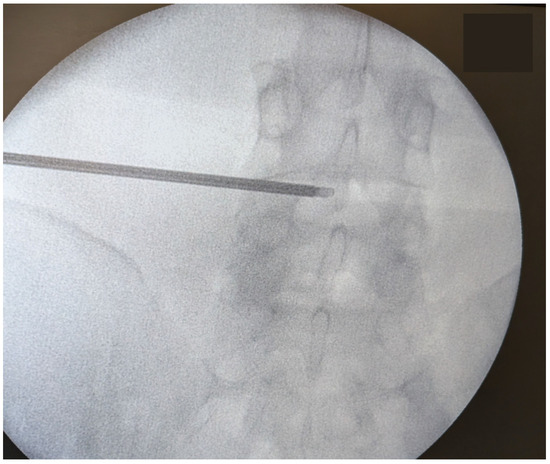

2.5. Surgical Procedure